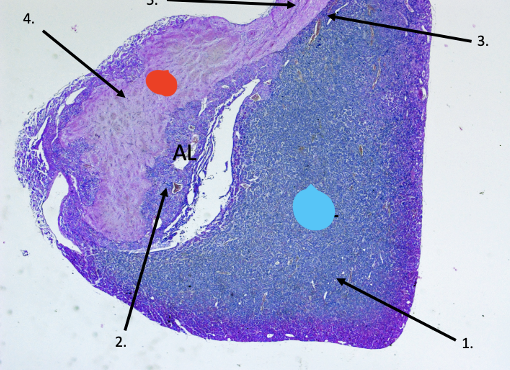

Pituitary gland

Red –> posterior lobe

Blue –> anterior lobe

Pars distalis

Chromophobes –> black arrows

Acidophils –> brown arrows

Basophils –> red arrows